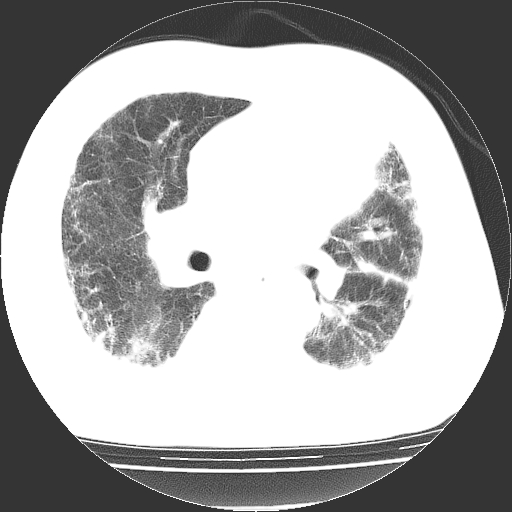

男,68岁,咳嗽、胸闷、发烧三天,查体:双肺散在湿罗音。

首先考虑特发型肺间质纤维化;两侧少量胸腔积液。

依据:1、两肺广泛条索状、网格状、蜂窝状改变。

双肺多发条索状、网格状及小灶状密度增高影。考虑慢支合并感染.间质纤维化,双侧少量胸腔积液

两肺广泛条索状、网格状、蜂窝状改变。肺间质纤维化,肺心病,双侧胸腔积液